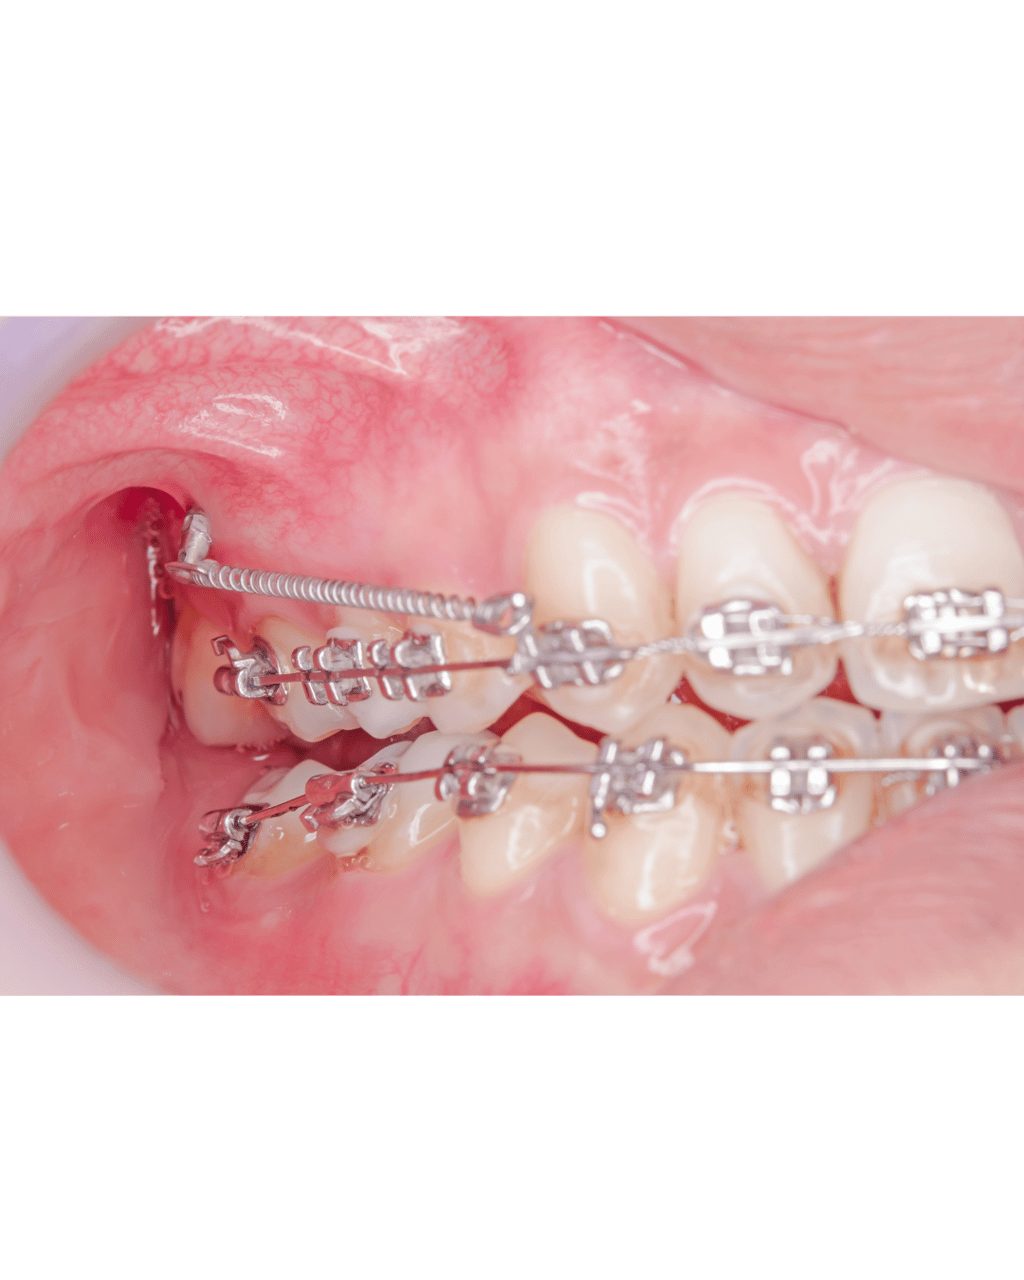

Mikroimplanty ortodontyczne – małe, biokompatybilne śruby, które stają się Twoimi niewidocznymi sprzymierzeńcami w dążeniu do perfekcyjnego uśmiechu!

Mikroimplanty zapewniają stabilne punkty zaczepienia dla sił ortodontycznych, umożliwiając precyzyjne i kontrolowane przesuwanie nawet najbardziej opornych zębów.

Wprowadzenie mikroimplantu jest prostym i bezbolesnym zabiegiem, wykonywanym w znieczuleniu miejscowym. Po zabiegu możesz wrócić do codziennych aktywności.